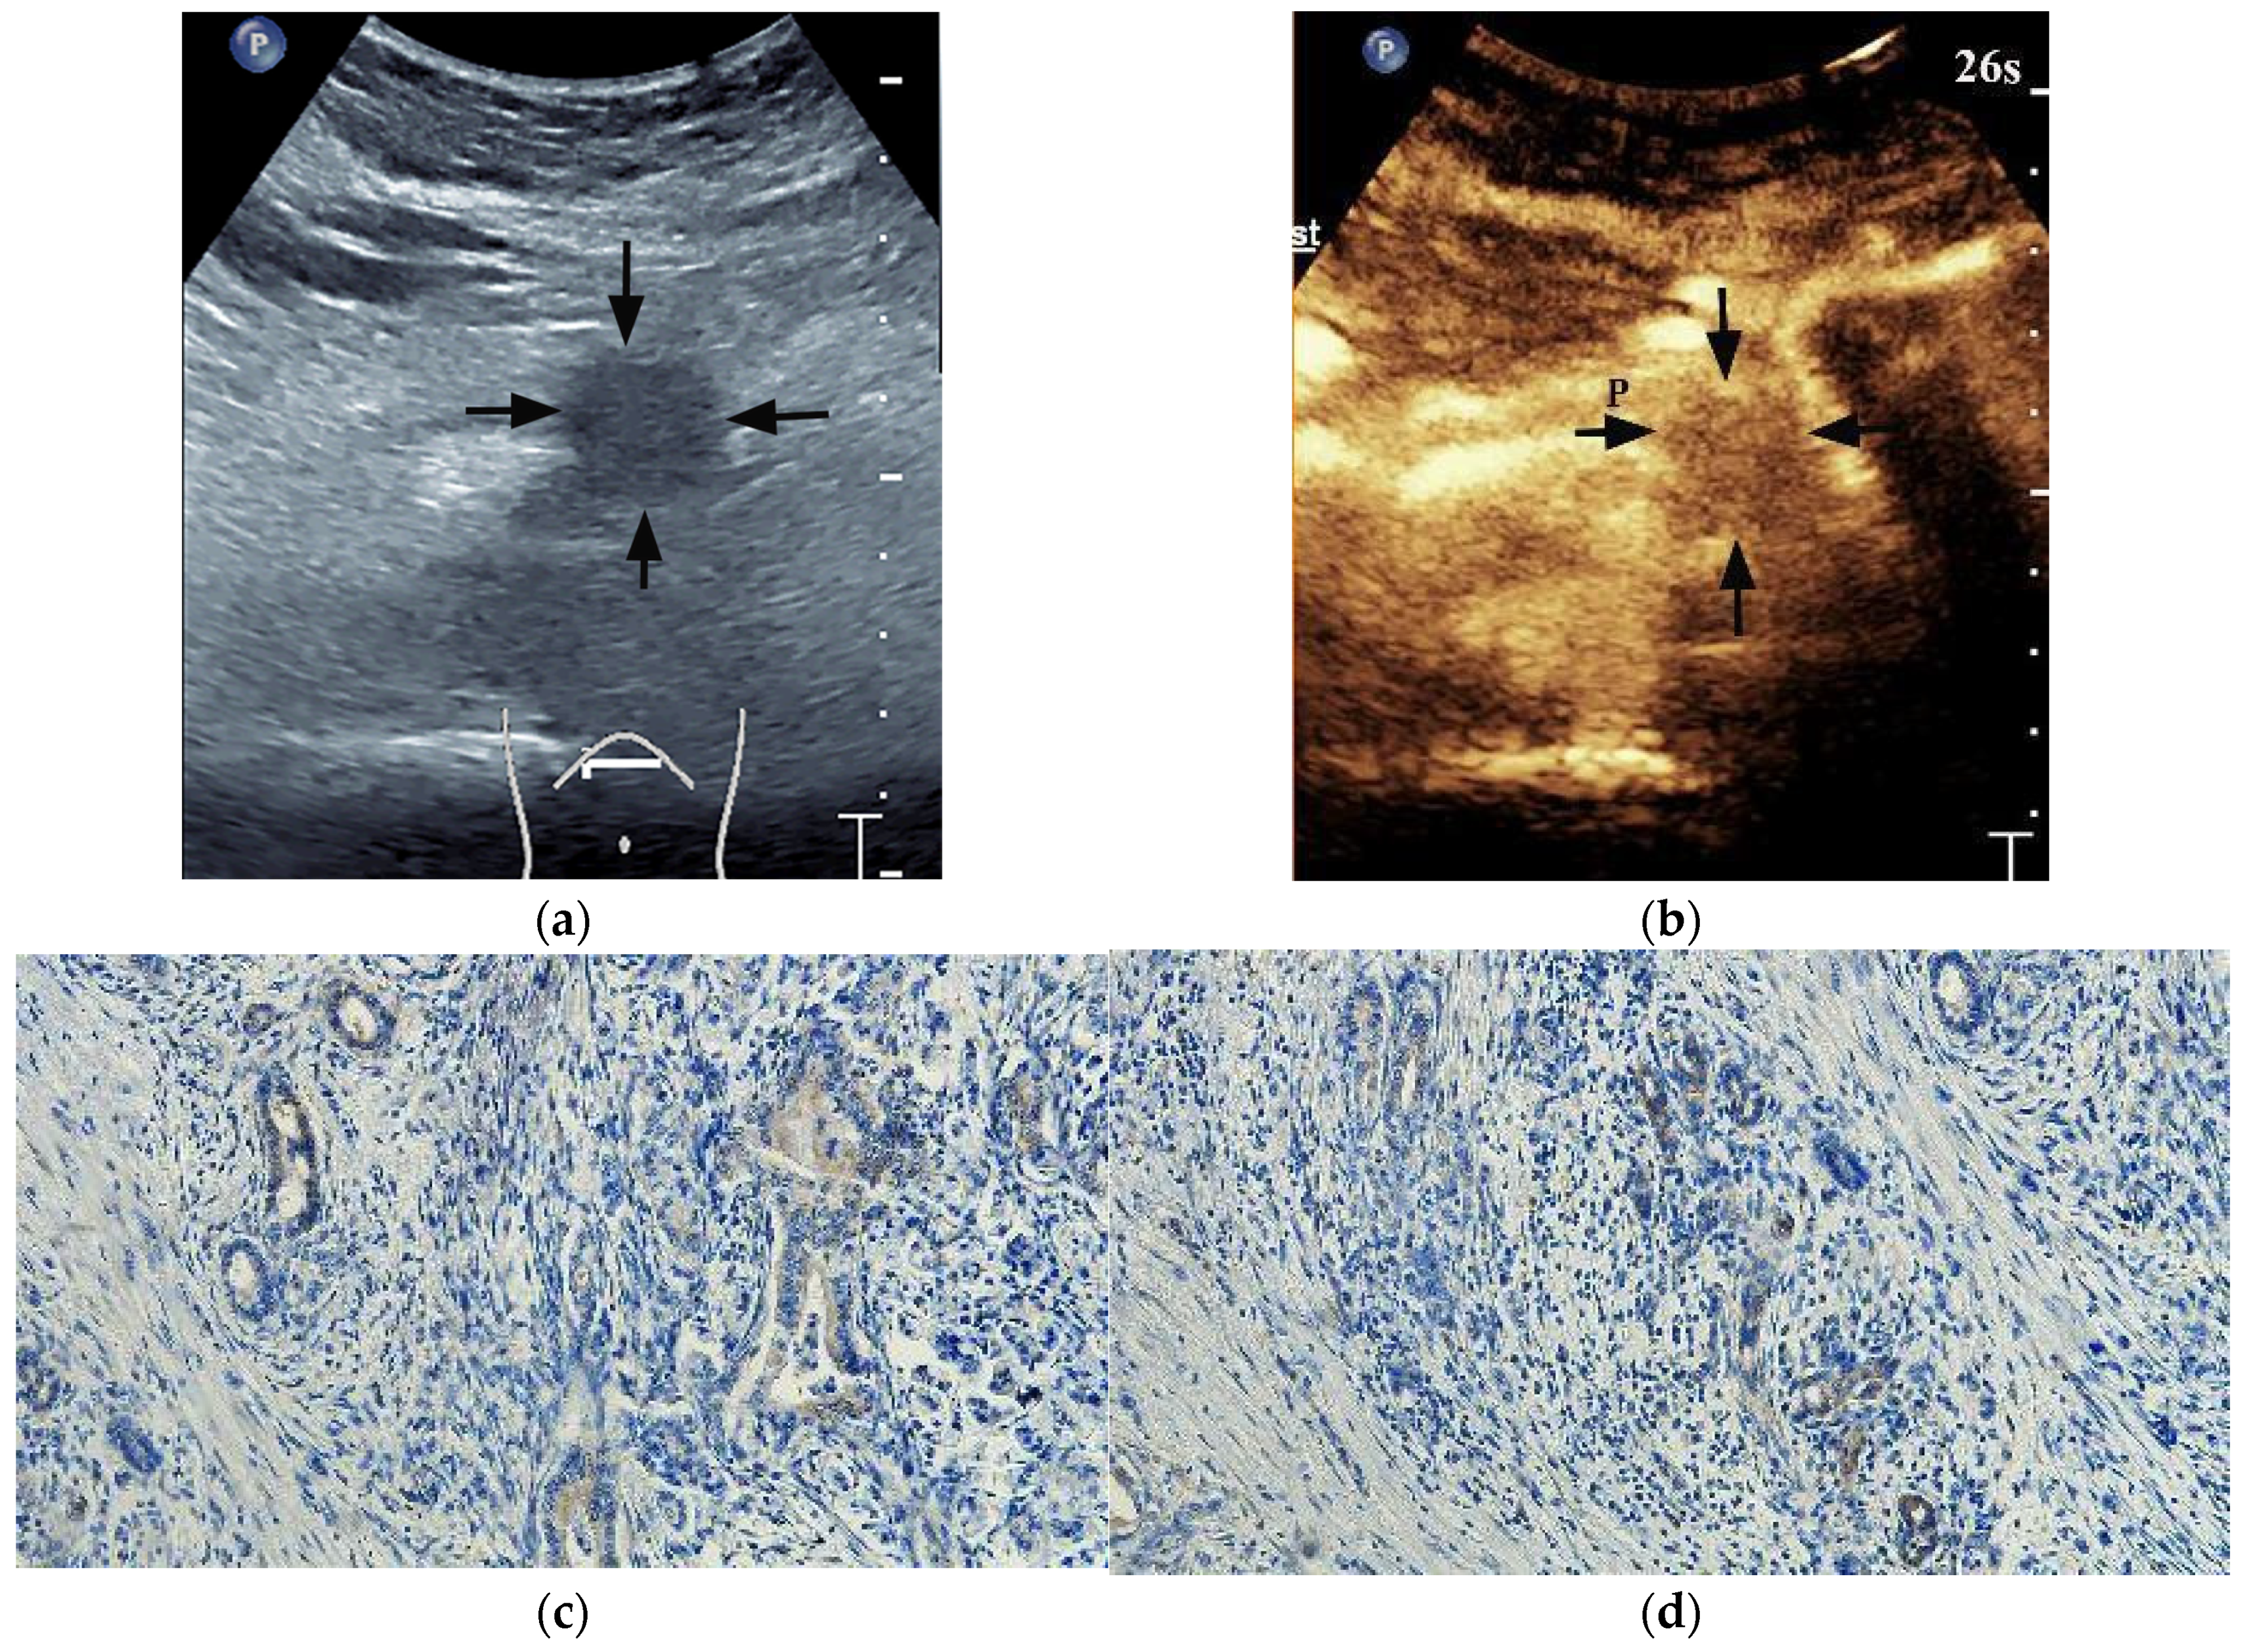

A quantitative analysis of CEUS was performed using the Software VueBox Quantification Toolbox (version 4.3). A total of 72 of 102 lesions obtained the ROIs parameters. Among the 72 cases of PDAC, 24 cases showed both high HIF-1α and GLUT1 high expression, 21 cases showed both low HIF-1α and GLUT1 low expression, 12 cases showed high HIF-1α but GLUT1 low expression, and 15 cases showed low HIF-1α but GLUT1 high expression. Both HIF-1α-high PDACs and GLUT1-high PDACs showed higher peak enhancement (PE) (p = 0.024 and p = 0.018, respectively) (Figure 5 and Figure 6) and higher wash-in rate (WIR) values (p = 0.015 and 0.002, respectively) (Table 5) more frequently. There were no significant differences in rise time (RT), time to peak (TTP) and wash-in area under the curve (WiAUC) between HIF-1α or GLUT1 high and low expression PDACs (p > 0.05 for all).

Figure 5. A 60-year-old male patient with a pancreatic ductal adenocarcinoma. (a) US revealed a hypoechoic lesion (arrows) at the pancreatic head. (b) The lesion (arrows) showed iso-enhancement of PED on CEUS. P = normal pancreatic parenchyma. (c) Time intensity curve analysis demonstrated a higher peak enhancement value (21,946.5 [a.u.]). (d) Photomicrographs of immunohistochemistry stain sections demonstrated a HIF-1α high expression ductal adenocarcinoma (original magnification, ×200). (e) Photomicrographs of immunohistochemistry stain sections demonstrated a GLUT1 high expression ductal adenocarcinoma (original magnification, ×200).